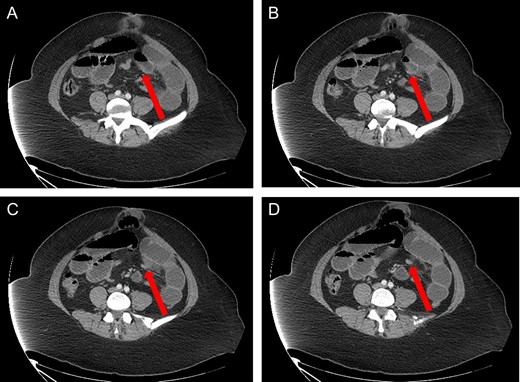

Axial view: (A) and (B) arrows pointing to dilated small bowel from the closed loop obstruction. (C) and (D) arrows pointing to the transition point, where the small bowel is collapsed distally.

A 40-year-old woman presented to the emergency department with abdominal pain for 4 days. She had previously been seen at an outside hospital 3 days earlier, and was diagnosed with biliary colic. Her pain was constant, and was associated with nausea and vomiting. She had a history of a cesarean section, but no other abdominal surgeries. Her vitals were within normal limits: afebrile at 36.9°C, heart rate 71 beats/minute, blood pressure 143/62 mmHg, respiratory rate 18 breaths/minute, and oxygen saturation 97% on room air. On abdominal exam, she was distended, tender, demonstrated voluntary guarding and was positive for peritonitis. Laboratory values were significant for a white blood cell count of 16.1 K/ul, with 80.2% neutrophils, hemoglobin 14.9 g/dl, hematocrit 45.4%, platelets 349 K/ul and lactic acid 0.9 mEq/L; her chemistry was unremarkable. A computed-tomography (CT) scan of the abdomen and pelvis that was obtained prior to surgical consultation demonstrated the proximal two-thirds of small bowel dilated up to 4 cm, with a sharp transition point in the left mid-abdomen, and collapsed small bowel loops near the cecum. The colon was mostly collapsed. A few distended loops bulged into a paraumbilical hernia, which was 6 cm wide and not the cause of obstruction (Figs 1–3).

Our patient again presented with obstructive symptoms and leukocytosis; however, unlike the previously reported cases, our patient did have prior abdominal surgery (cesarean section). After eliciting peritonitis on exam, and reviewing the dumb-bell shaped small bowel obstruction on CT, we immediately took the patient for a laparotomy. Interestingly, she did not have full thickness necrosis of her bowel despite the presence of peritonitis on exam; however, it was clear intra-operatively that her threatened bowel would have progressed to complete strangulation and bowel necrosis without emergent intervention.